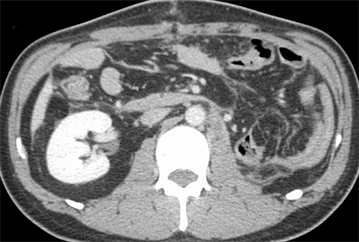

A 47-year-old man was referred to our institute with an enlarging left RCC. Computed tomography scanning revealed a large enhanced mass in the left kidney (Figure 1(a)) and local extension into the infrahepatic IVC (Figure 2) with pulmonary tumor embolism (Figure 3(a)). The embolism was located at the proximal portion of the right pulmonary artery, with no suspicious lesions in the left lung. As the mass of the RCC had been rapidly increasing in size for the past 2 months, early surgery was scheduled.

After sufficient anticoagulant treatment, the patient was discharged without any complications (Figure 1(b), Figure 3(b)). He is currently doing well with no evidence of recurrent disease or other metastases at a follow-up of 10 months. Follow up computed tomography revealed no recurrences and other metastases.

Figure 1. (a) Preoperative computed tomographic scan showing a large enhanced mass in the left kidney; (b) Postoperative computed tomographic scan showing no recurrences and other metastases.